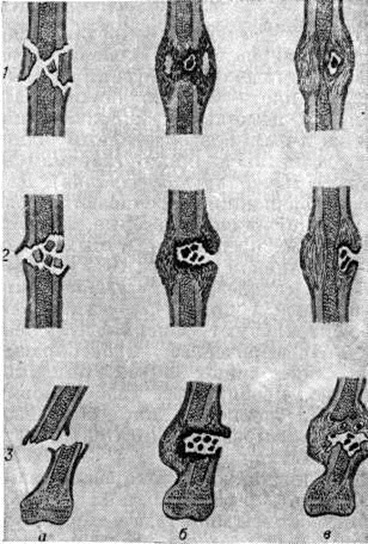

В других случаях наблюдается инкапсуляция гнойников в кости. К 3—4-й недель от начала заболевания при рентгенологическое исследовании на фоне рарефикации определяются очаги некроза кости, поскольку омертвевшая кость не подвергается резорбции и сохраняет прежнюю плотность. При патологоанатомическом исследовании участки некроза выявляются ещё раньше. В дальнейшем те из них, которые находятся в самом очаге нагноения, подвергаются секвестрации (рисунок 1). Секвестрация (смотри полный свод знаний Секвестр, секвестрация) заключается в отторжении омертвевших участков кости, находящихся в полости гнойника, от окружающей костной ткани. При этом в случае образования секвестра в компактной пластинке на её поверхности в зоне прилегания грануляций возникает и постепенно углубляется секвестральная борозда, а в толще — расширение гаверсовых каналов и слияние их между собой. После того как все костное вещество в указанной зоне растворится, секвестр оказывается свободно лежащим в полости гнойника (цветной рисунок 2 и 3). Секвестры губчатого вещества кости отделяются от остальной её части за счёт растворения прилежащих костных балок, находящихся в зоне грануляций (рисунок 2).

Огнестрельный Остеомиелит характеризуется нагноением в зоне огнестрельного перелома кости, которое сопровождается образованием секвестров и регенерацией тканей. На основании анализа клинико-анатомических особенностей огнестрельного остеомиелита П. Г. Корнев выделяет три этапа его динамики: 1) острое воспаление в краях раны с отграничением и частичным расплавлением некротизированных тканей; 2) формирование гнойного очага вокруг некротизированных и секвестрирующихся участков кости с образованием гноеродной оболочки, а в ряде случаев и костной мозоли; 3) образование и длительное существование гнойного очага после сращения перелома и восстановления функции повреждённого органа.

Воспаление начинается в мягких тканях краёв раны в виде диффузной воспалительной инфильтрации, вслед за которой на границе с зоной омертвения формируется демаркационная линия. Одновременно образуется экссудат, поступающий в полость раны и пропитывающий некротизированные ткани, подвергающиеся при этом расплавлению, а часто и гнилостному распаду. К 4— 5-му дню в зоне демаркационной линии образуются грануляции, обильно продуцирующие гной. К этому сроку проявляется и гнойное воспаление в отломках кости, которое протекает на границе с некротизированными тканями, сохраняя характер демаркационного. С началом нагноения омертвению могут подвергнуться связанные с периостом костные осколки и мягкие ткани, испытавшие коммоцию — зона резерва некроза по И. В. Давыдовскому. Очаг нагноения постепенно изолируется валом из грануляций, а в последующем и соединительнотканной капсулой. В нем располагаются свободные костные осколки, не удалённые при хирургической обработке раны, осколки, сохранившие связь с периостом, концы отломков, лишённые периоста, инородные тела, обрывки мягких тканей, распадающиеся кровяные свёртки (рисунок 3). Нагноение нередко распространяется в глубь мягких тканей и в толщу кости вдоль трещин и каналов, проделанных сместившимися в момент ранения костными осколками, что придаёт очагу сложные очертания (цветной рисунок 1).

В ходе нагноения в окружающих очаг тканях развёртываются пролиферативные и дистрофические процессы. В результате пролиферации тканей возникает гноеродная оболочка, а затем формируется костная мозоль (смотри полный свод знаний) с последующей консолидацией перелома или образуются лишь костные разрастания по краям отломков (рисунок 4). Возникшая костная мозоль включает в себя гнойники с секвестрами (цветной рисунок 2) и играет т. о. роль секвестральной капсулы, из которой свищевые ходы ведут на поверхность кожи (рисунок 5). Дистрофические изменения выражаются в диффузной рарефикации, а позже в очаговой эбурнеации кости (смотри полный свод знаний) в зоне образования мозоли. В окружающих мягких тканях и в соседних суставах развиваются явления атрофии.